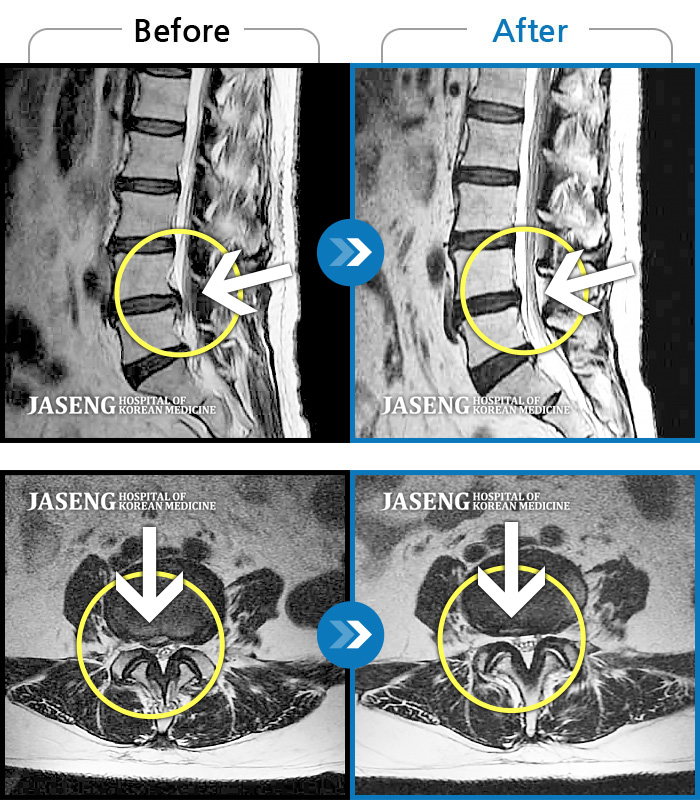

60건의 MRI 전후 사진으로 터진 디스크 흡수 사례를 확인하세요.

※ 환자분에게 사전 동의를 받아 동일 조건에서 촬영되었으며, 개인에 따라 치료 후 부작용이 발생할 수도 있으니 사전에 의료진과 상담 후 치료를 진행하시기 바랍니다.